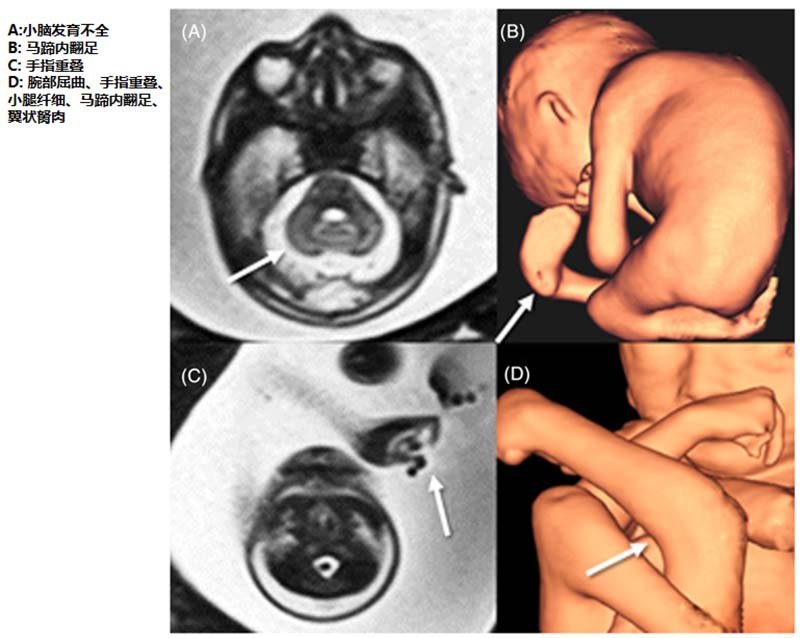

图3.妊娠22周+4天时进行的胎儿MRI检查